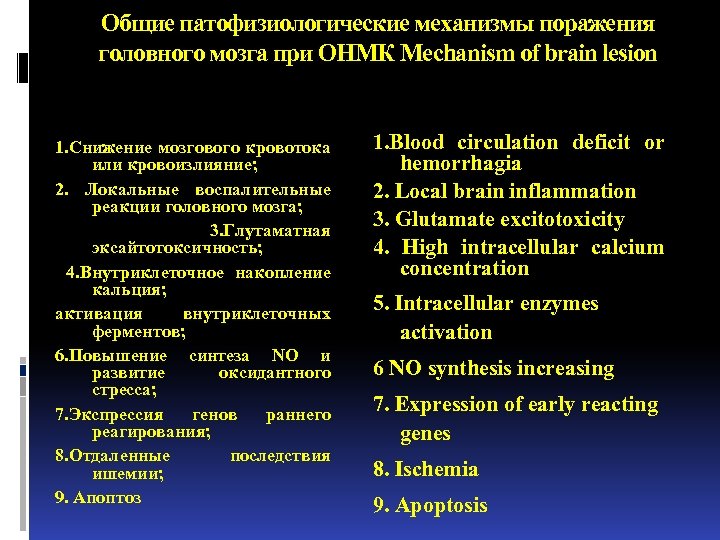

Общие патофизиологические механизмы поражения головного мозга при ОНМК Mechanism of brain lesion 1. Снижение мозгового кровотока или кровоизлияние; 2. Локальные воспалительные реакции головного мозга; 3. Глутаматная эксайтотоксичность; 4. Внутриклеточное накопление кальция; активация внутриклеточных ферментов; 6. Повышение синтеза NО и развитие оксидантного стресса; 7. Экспрессия генов раннего реагирования; 8. Отдаленные последствия ишемии; 9. Апоптоз 1. Blood circulation deficit or hemorrhagia 2. Local brain inflammation 3. Glutamate excitotoxicity 4. High intracellular calcium concentration 5. Intracellular enzymes activation 6 NO synthesis increasing 7. Expression of early reacting genes 8. Ischemia 9. Apoptosis

Общие патофизиологические механизмы поражения головного мозга при ОНМК Mechanism of brain lesion 1. Снижение мозгового кровотока или кровоизлияние; 2. Локальные воспалительные реакции головного мозга; 3. Глутаматная эксайтотоксичность; 4. Внутриклеточное накопление кальция; активация внутриклеточных ферментов; 6. Повышение синтеза NО и развитие оксидантного стресса; 7. Экспрессия генов раннего реагирования; 8. Отдаленные последствия ишемии; 9. Апоптоз 1. Blood circulation deficit or hemorrhagia 2. Local brain inflammation 3. Glutamate excitotoxicity 4. High intracellular calcium concentration 5. Intracellular enzymes activation 6 NO synthesis increasing 7. Expression of early reacting genes 8. Ischemia 9. Apoptosis